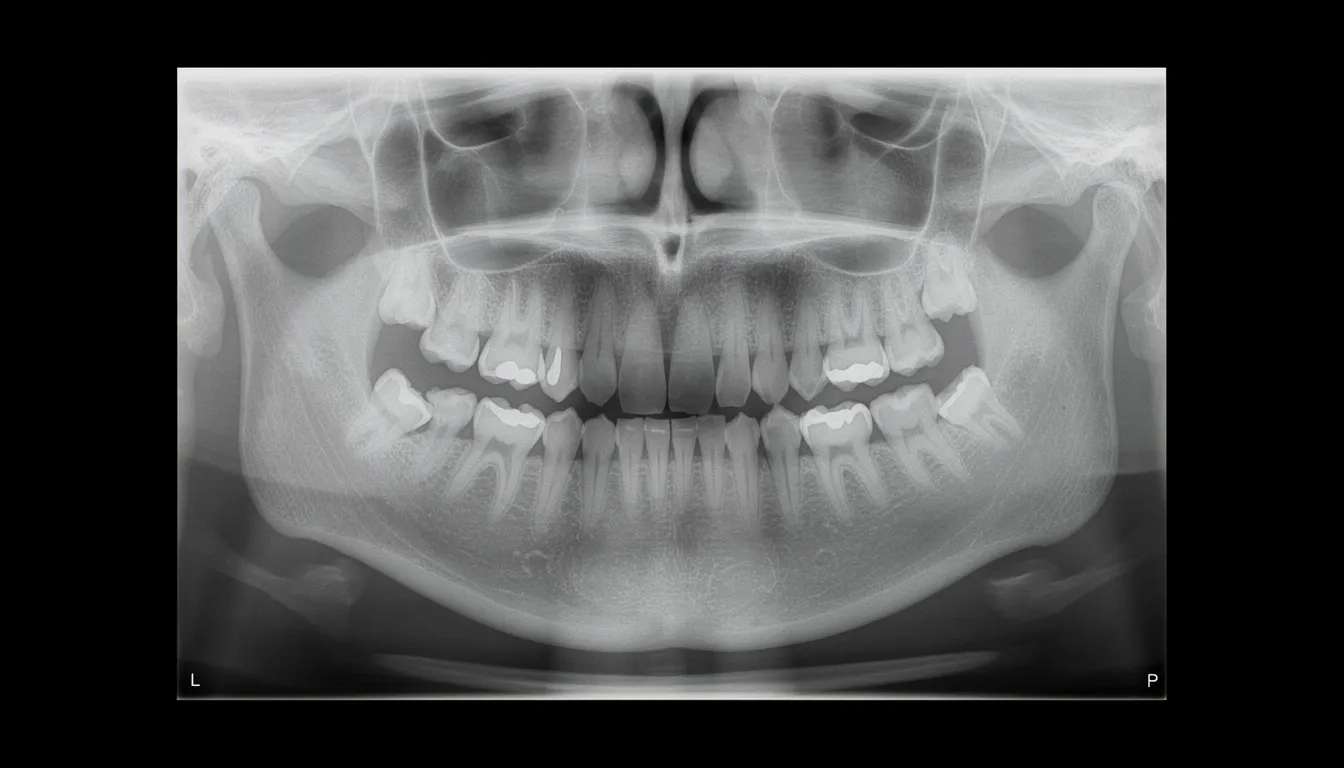

During your exam, our team reviews X-rays and evaluates your tooth to determine which type of extraction you need. This classification directly affects both the procedure time and the extraction cost.

A thorough dental exam and necessary X-rays to evaluate roots, bone, and nearby nerves or sinuses